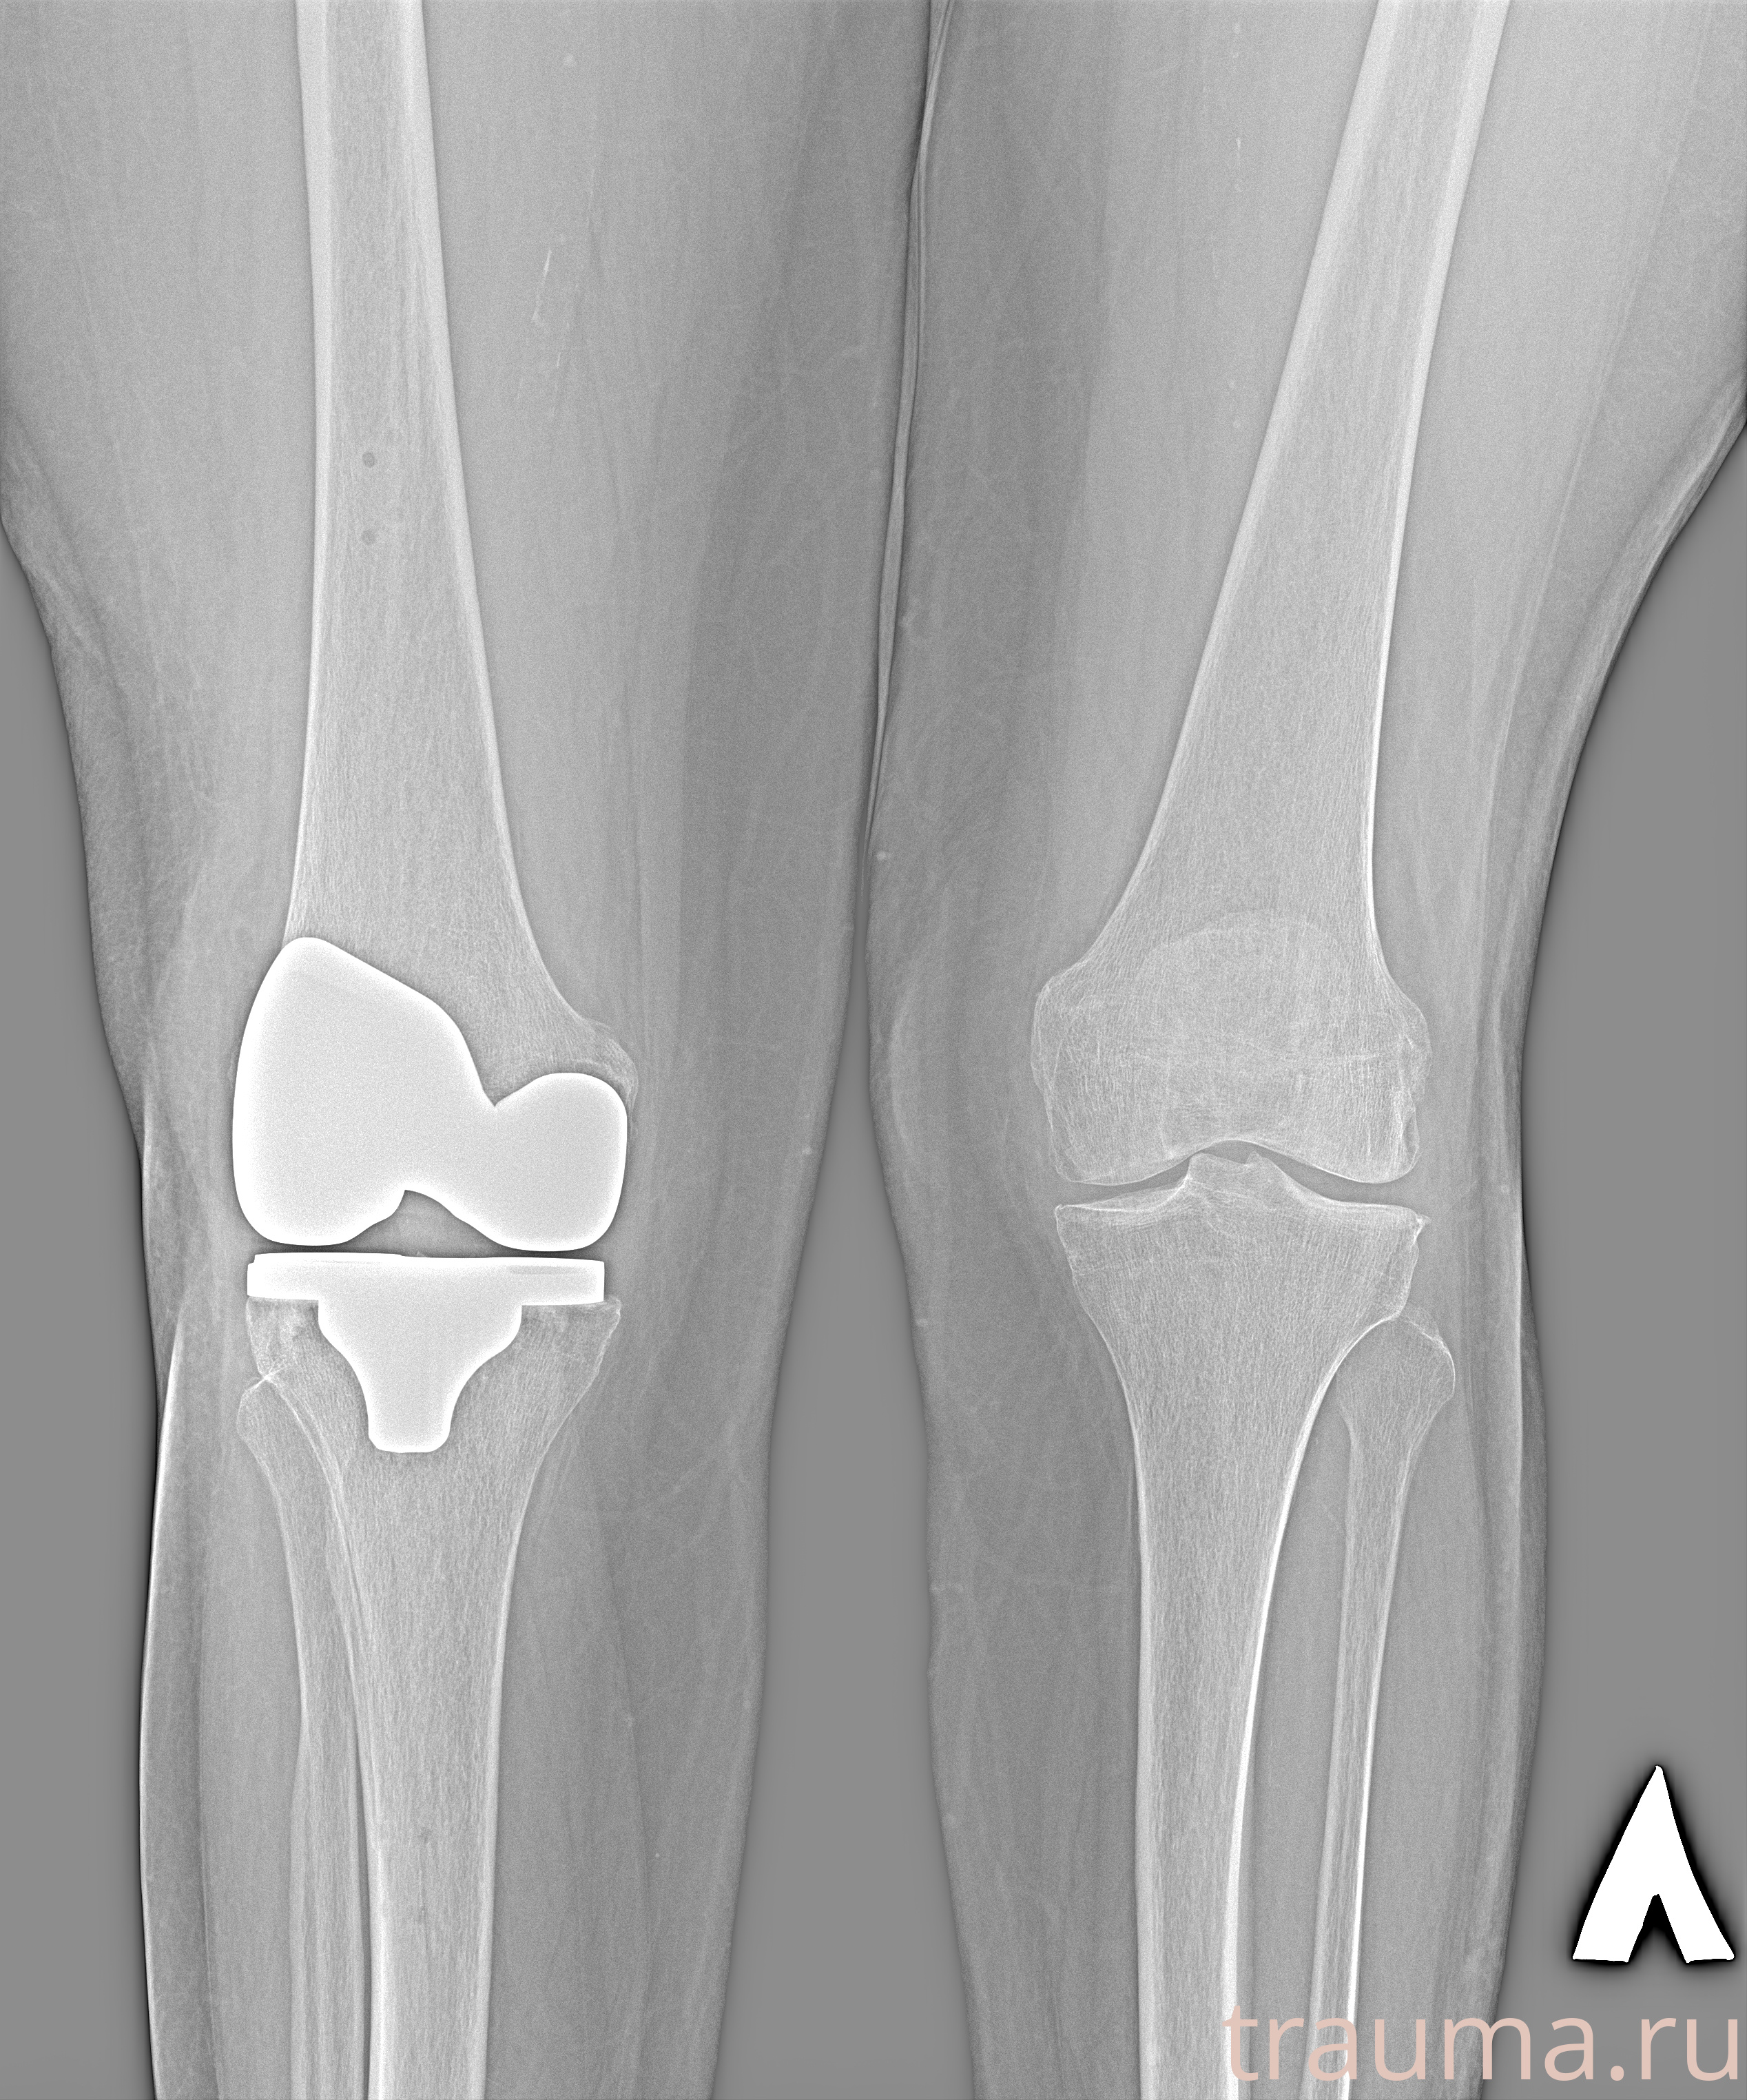

Рентгенограммы

Рентген на дому: по вашему адресу приезжает врач-рентгенолог, травматолог-ортопед с мобильным рентгеновским аппаратом, проводит диагностику травмы или заболевания, делает необходимые рентгенограммы, дает рекомендации по дальнейшему лечению. Получить качественные снимки в домашних условиях возможно благодаря уникальной методике, разработанной МосРентген Центром для института  Склифосовского